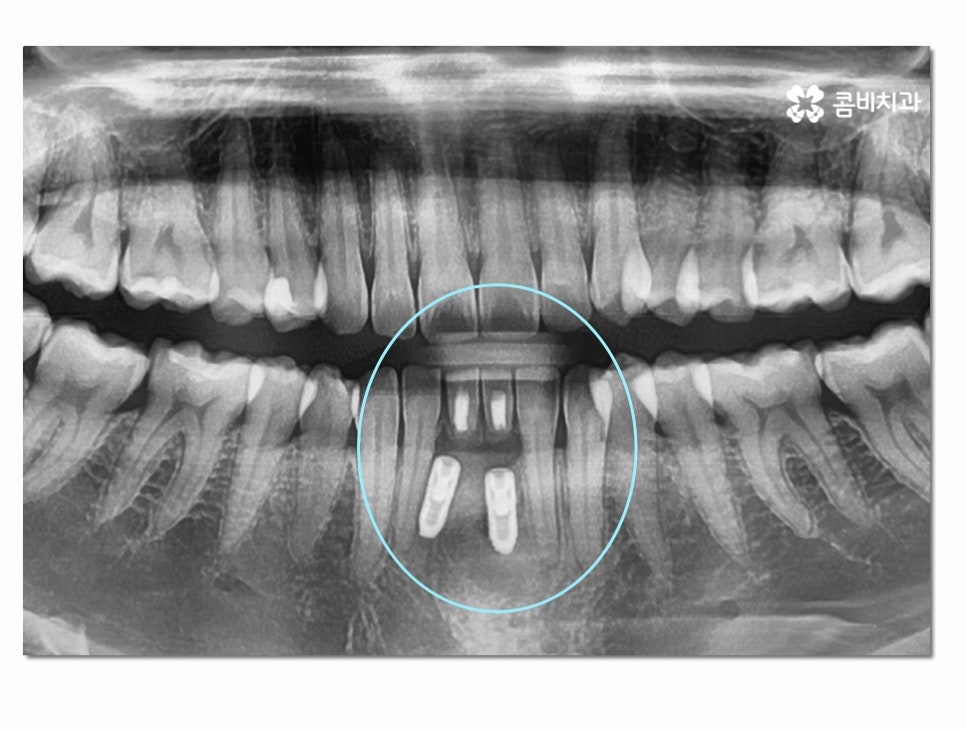

위 사진은 인공치근이 식립된 상태이고 인공치근이

잇몸뼈와 잘 유착이 되는지 확인하는 기간을

갖는 것이며 보철물을 결합하기 전에는 임시치아를 부착하고 있어요.

(좌 - 임플란트 식립 후 임시치아를 부착하고 안전하게 골 유착이 되도록 기다리는 과정, 보철물과 결합 준비 - 우)

인공치근이 튼튼하게 자리를 잡게 된 것이 확인이 되면

보철물을 주변 치아의 색과 모양과 비슷하게 제작하여

결합하는 과정을 거치고 아랫니 임플란트 치료 과정이 마무리될 수 있어요.